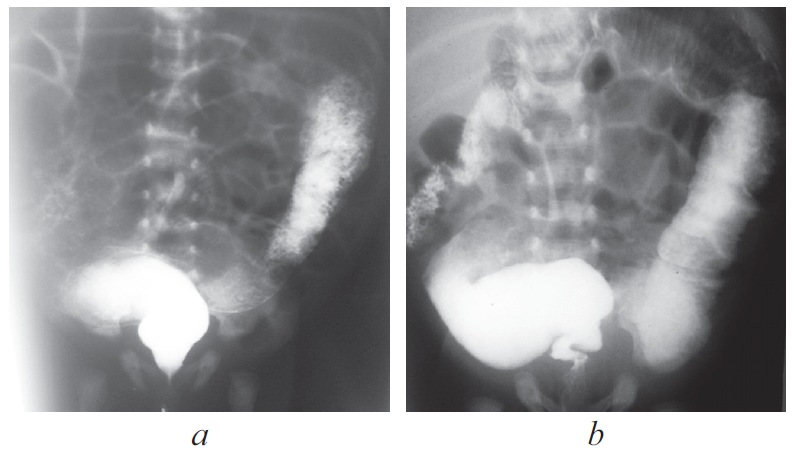

Доношенный ребенок поступил в возрасте 3 сут жизни с клиникой кишечной непроходимости: срыгивания с примесью желчи, вздутие живота, отсутствие стула. Осмотр промежности ребенка не вызвал вопросов у хирурга, по клинико-рентгенологическим данным была заподозрена болезнь Гиршпрунга. Ежедневно выполнялись очистительные клизмы. Контрастное исследование толстой кишки произведено в возрасте 14 дней жизни. По данным ирригографии выявлено резкое расширение дистального отдела сигмовидной кишки (рис. 4).

Рис. 4. Ирригография

Fig. 4. Contrast enema

Ирригография является обязательным исследованием у всех детей с подозрением на болезнь Гиршпрунга [2]. Чувствительность и специфичность метода по литературным данным достигает 70 и 80 % соответственно. Хорошо известно, что диагностическая значимость ирригографии в определении переходной зоны у новорожденных с болезнью Гиршпрунга меньше, чем у детей более старшего возраста (65 против 75 %) [3]. I.R. Diamond et al [4]. описали возможные предрасполагающие факторы получения ложноположительных результатов при выполнении контрастного исследования у пациентов с болезнью Гиршпрунга, одним из них является возраст ребенка. У детей в возрасте 30 сут жизни было больше ложноположительных результатов, чем у пациентов младшего возраста. Срок выполнения рентгенологического обследования зависит от нескольких факторов, главным из которых является эффективность опорожнения толстой кишки. Обследование целесообразно выполнять не сразу после поступления новорожденного в стационар, а отсроченно, после купирования явлений Гиршпрунг-ассоциированного энтероколита, чтобы исключить сужение кишки, связанное с ее спазмом на фоне воспалительных явлений. Конечно, это не касается ситуаций, когда есть клиника некупирующейся кишечной непроходимости, либо признаки «токсического» мегаколона. В этих случаях ирригография обязательно проводится непосредственно при поступлении ребенка в стационар. В остальных случаях, когда декомпрессия кишечника эффективна, исследование может быть отложено на несколько дней, до полной стабилизации состояния и нормализации клинико-лабораторных показателей. Контрастирование толстой кишки у детей с клиникой низкой кишечной непроходимости носит не только диагностический, но и лечебный характер, особенно при синдромах мекониальной пробки и суженной левой половины толстой кишки, которые могут быть причиной для постановки ложноположительного диагноза болезни Гиршпрунга. Надо отметить, что ирригография, выполненная в первые дни жизни ребенка сразу после появления клиники непроходимости, и отсроченное исследование могут отличаться друг от друга. На представленных рентгенограммах одного и того же ребенка с разницей в две недели видны существенные различия (рис. 8, а, b). Если на первичной ирригограмме можно оценить лишь правильность расположения толстой кишки и наличие в ней большого количества содержимого, то при исследовании через 2 недели видны четкие признаки ректосигмоидной формы болезни Гиршпрунга с наличием зоны сужения и воронкообразным супрастенотическим расширением.

Рис. 8. Ирригография; а — вторые сутки жизни; b — две недели жизни

Fig. 8. Contrast enema. а – second day of life; b – two weeks of life